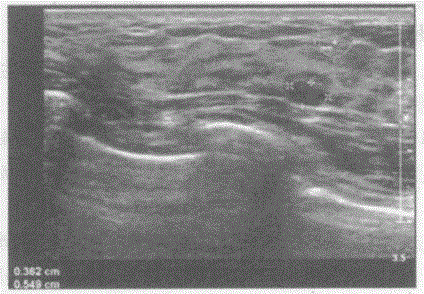

问题 临床资料:女,28岁,自诉双侧乳房胀痛。 超声综合描述:右乳腺腺体层厚1.1cm,左乳腺腺体层厚1.0cm,双乳腺腺体层结构紊乱,内可见大小不等管状无回声,右乳腺外下象限可见0.4cm×0.5cm低回声,右乳腺内上象限可见0.6cm×0.3cm低回声,边界清晰,形态规则。 超声提示:

选项 A.乳腺增生乳腺纤维腺瘤 B.乳腺增生病乳腺癌 C.乳腺增生病(囊实性) D.乳腺囊肿

答案 C